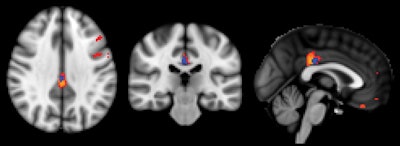

Initial ASL-MRI scans showed decreased cerebral blood flow in the posterior cingulate cortex region of the brain in approximately half of the healthy subjects in the study, who later developed subtle cognitive decline.

The posterior cingulate cortex is associated with the default mode network, which is active when the brain is not concentrating on a specific task. Less perfusion indicates decreased neural activity; thus, declines in this network are seen in patients with mild cognitive impairment and are more pronounced in those with Alzheimer's disease.

At the 18-month follow-up, the researchers found that 75 subjects had remained stable. The remaining 73 had deteriorated cognitively and also showed reduced perfusion in their ASL-MRI exams at baseline, particularly in the posterior cingulate cortex.